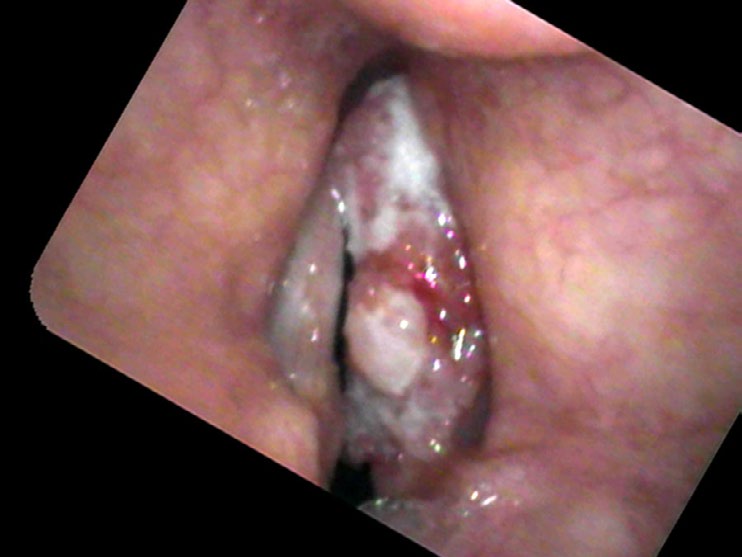

Stefan Kowal developed hoarseness two years ago. He had been seen twice by a laryngologist who told him he had a polyp on the right vocal cord and treated him with antibiotics, reassuring him it wasn’t cancer. His vocal quality fluctuated, such that at times he thought he was improving. Then he definitely became more hoarse. He now cannot yell or even be heard well with any background noise and he develops pain if he speaks very much.

Physicians may over or underestimate the possibility of cancer. Some, who do not want their patients to be concerned, might underestimate the risk of cancer; others bring up the probability of cancer such that surgery seems like the smaller risk than the uncertainty of not knowing. In Mr. Kowal, I was in awe how such a large mass, covering the entire surface of one vocal cord, could be examined two years in a row and still be treated as a polyp. I suspect that equipment played a role, as the flexible fiberoptic scope found in many offices presents a blurry picture. There was no recording made of his prior exams; quite possibly the image in the eyes of the otolaryngologist was fleeting. Couple the problems of no recording and a blurry view with the possibility that the physician did not move the endoscope very close to the vocal cords and the delay in diagnosis is now understandable, even if not desirable.

- Squamous cell carcinoma of the vocal cord often presents with progressive hoarseness, pain with voice use, and an irregular, pebbled surface — but can be mistaken for a polyp without high-quality imaging.